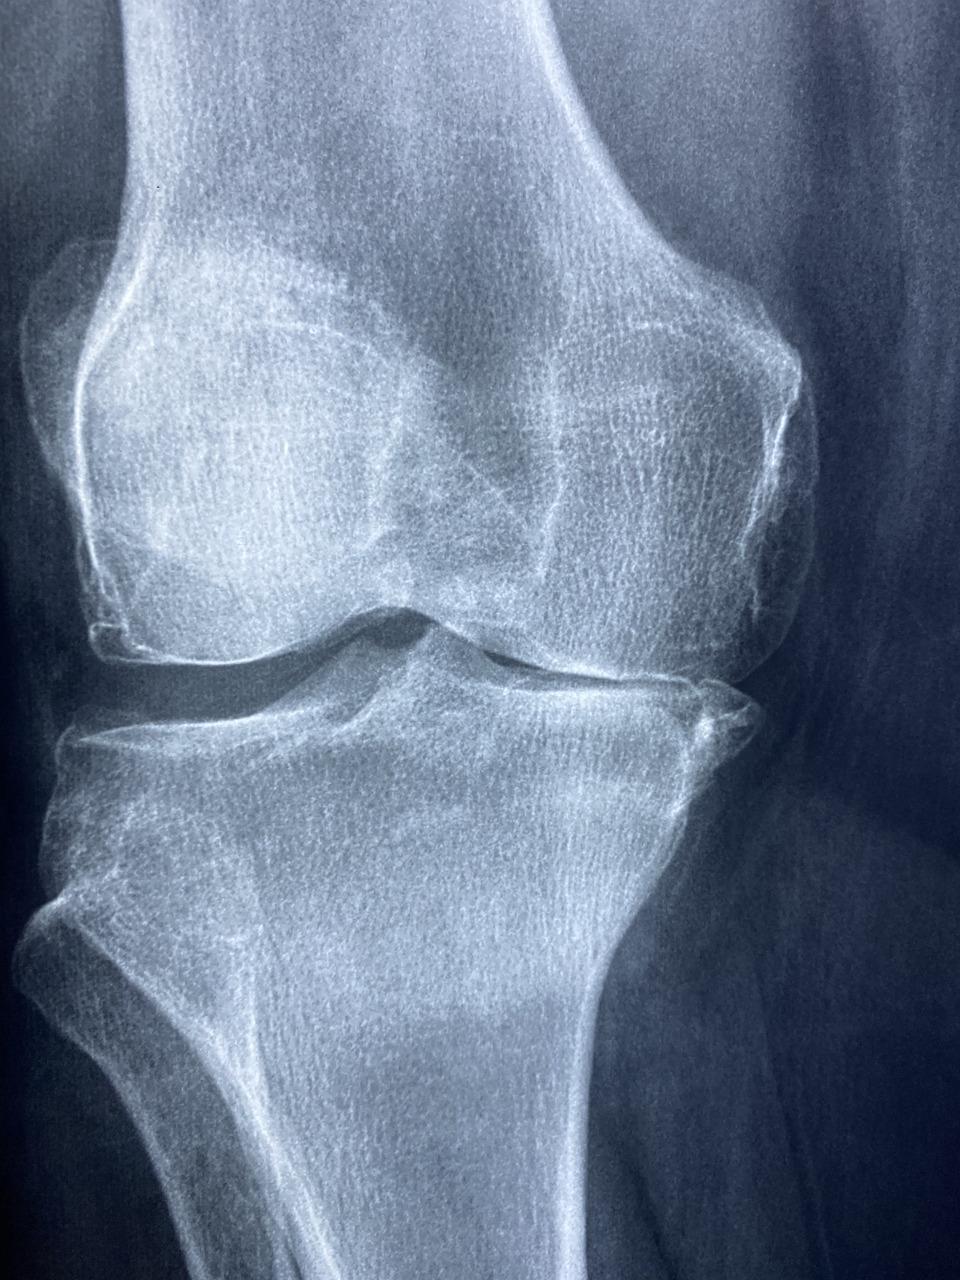

Over time tissues in the bones, which are made up of minerals such as calcium, break down and are slowly replaced by a natural process called bone turnover. This is how your bones grow and become strong from the time you are an infant to an adult. When osteoporosis occurs, however, the tissues break down at a faster rate than they are replaced, resulting in loss of bone strength and bone mass. When this happens bones become brittle and more likely to break. Osteoporosis usually affects the spine, hips, ribs and wrists, most commonly.